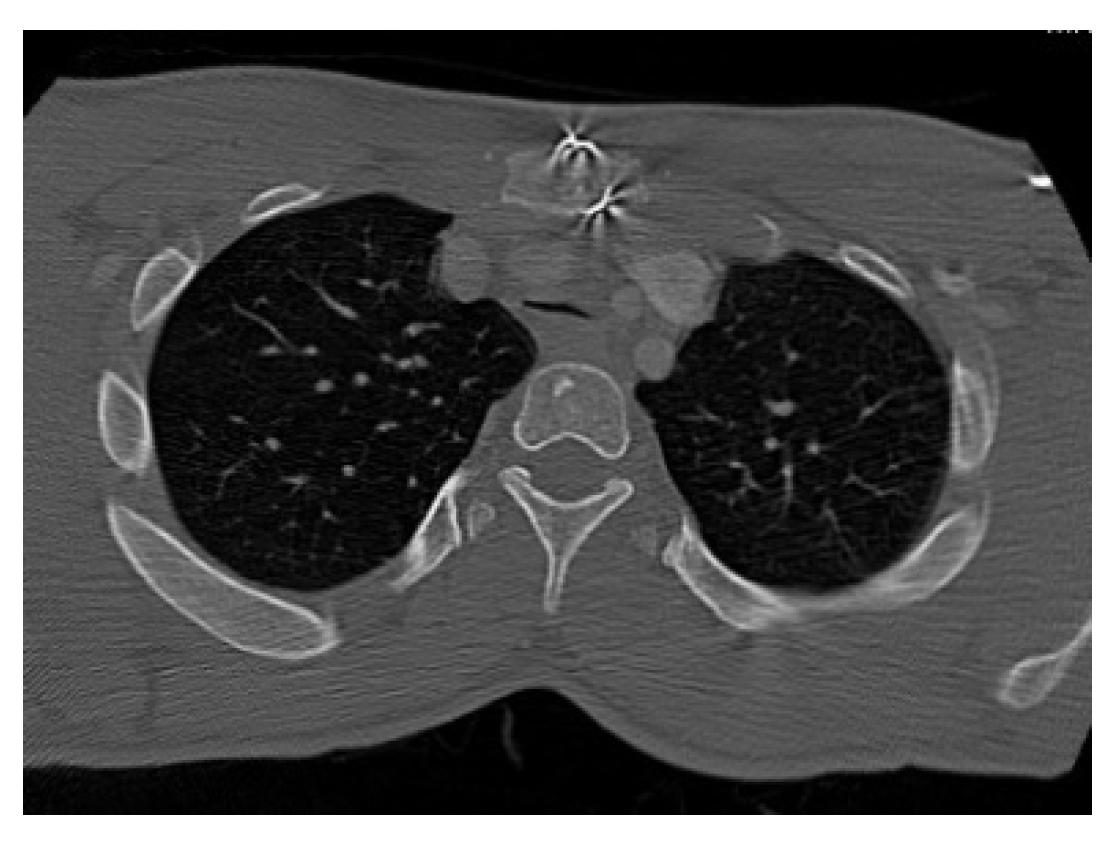

3.2. Cross-Sectional Imaging

3.3. 3-Dimensional Reconstruction (3D) and Virtual Endoscopy (VE)